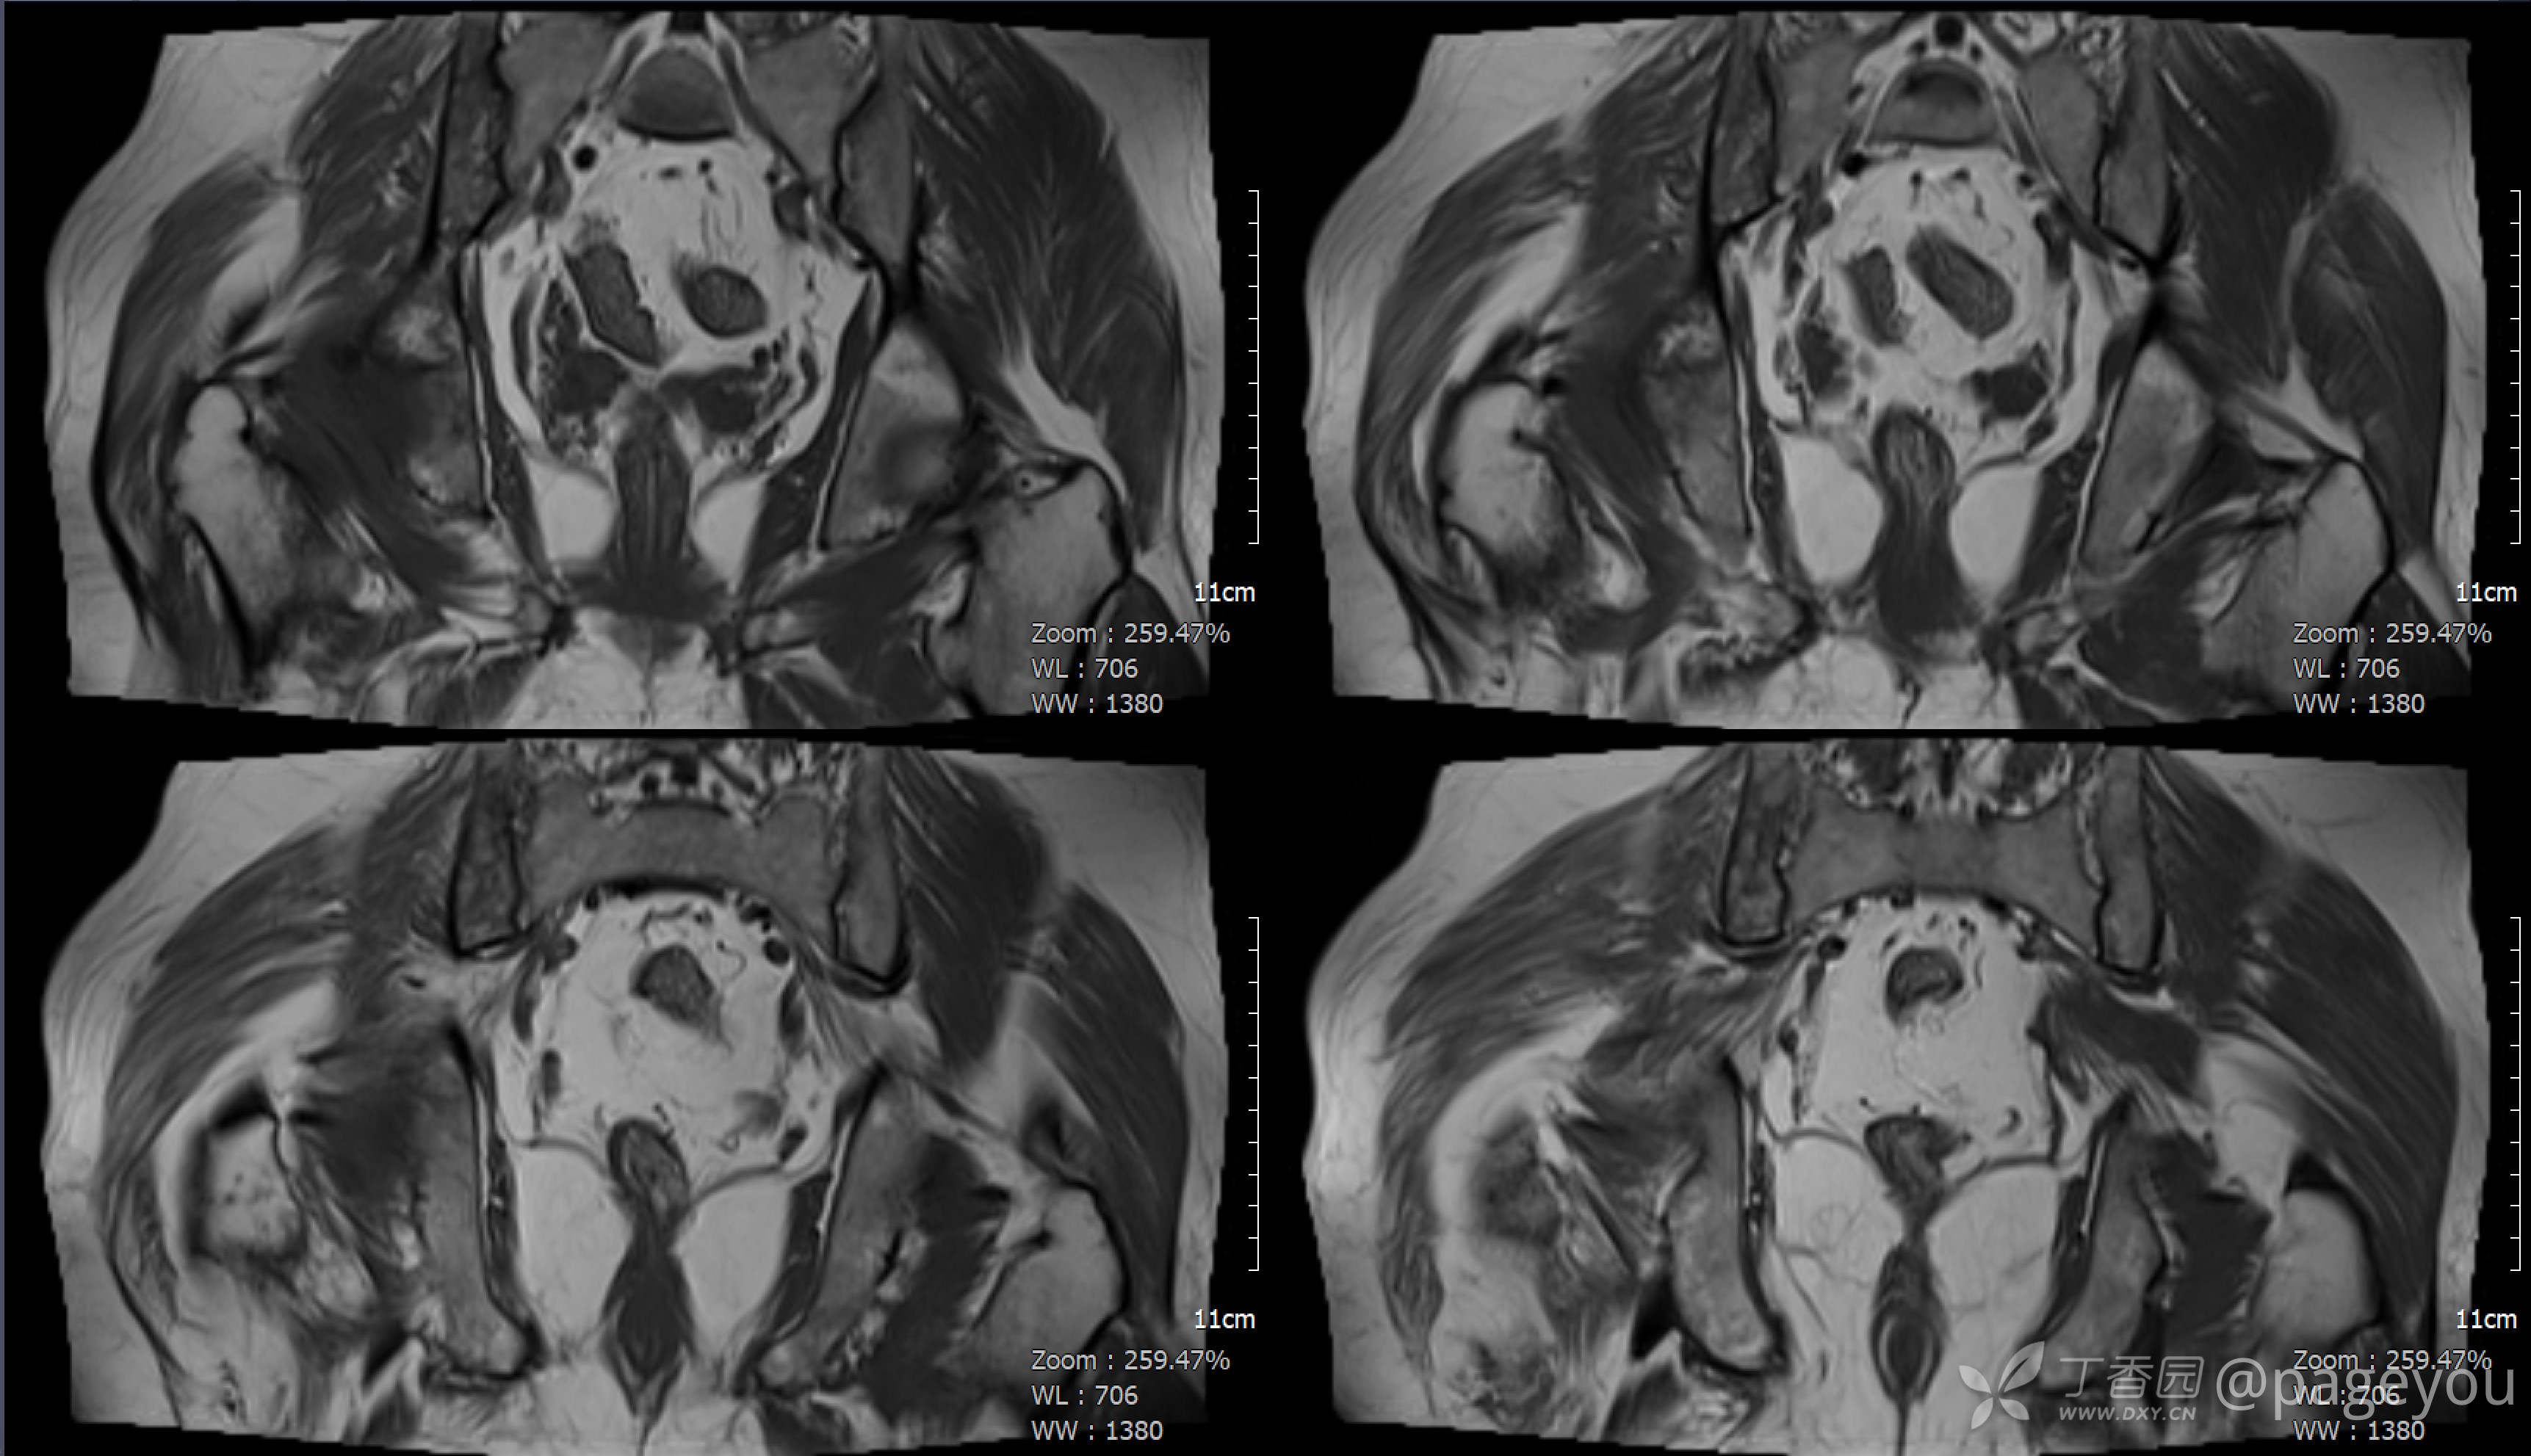

查骨盆MRI: